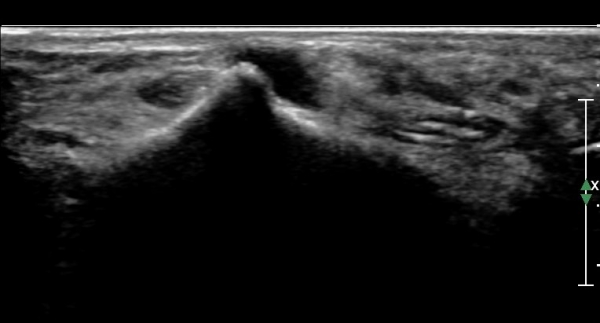

Á¾°ñºñ°ñÀδë Á¾´Ü¸é°Ë»ç¿¡¼­ °Å°ñÇϰüÀýÀÇ ¼ö¾×Àú·ù(Á¾°ñºñ°ñÀÎ´ë ½ÉºÎ ¼ö¾×Àú·ù)°¡

°üÂûµÈ´Ù(»çÁø 4).